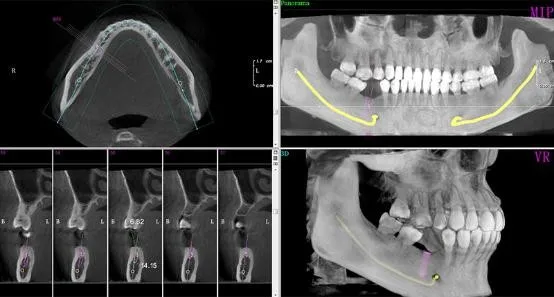

3d dental x ray. The 3d ct x ray scanning of dental impressions is traditionally a very time consuming process. Three dimensional x rays capture a true 3 d image of the mouth and allow a dentist to study the mouth in slices similar to a ct scan. Dental cone beam computed tomography ct also known as cone beam computed tomography cbct is a type of dental x ray equipment that takes panoramic 3d images of your teeth gums soft tissues and nerve pathways in a single scan. X ray imaging including dental 3d cbct provides a fast non invasive way of answering a number of clinical questions.

Three dimensional x rays sometimes referred to as a cone beam capture images of the teeth and mouth. Your doctor may use this technology to produce three dimensional 3 d images of your teeth soft tissues nerve pathways and bone in a single scan. Dental cbct images provide three dimensional 3d information rather than the two dimensional 2d information provided by a conventional x ray image. Filter by popular features pricing options number of users and read reviews from real users and find a tool that fits your needs.

3d dental x rays use whats called cone beam computed tomography cbct to provide your. 3d dentals phosphor imaging plates are a digital imaging system that reads the x ray on a phosphor imaging plate and sends the image to your computer.